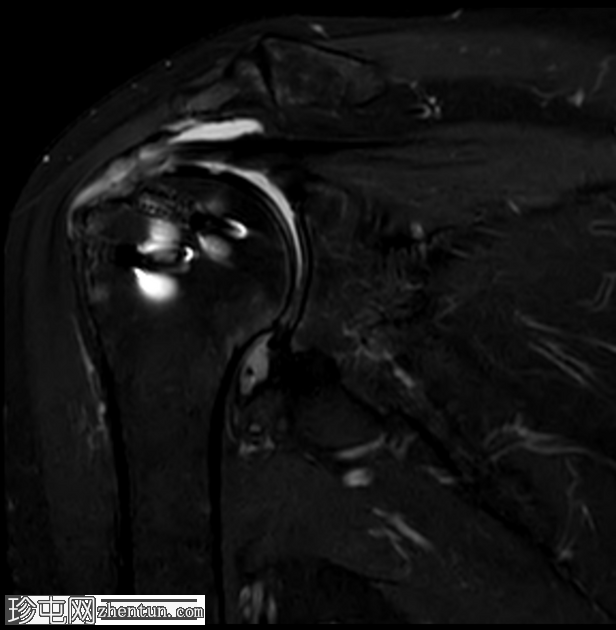

冠状位T2加权像

脂肪抑制像

T2加权像显示近端锚钉周围有液体信号,提示锚钉松动,这并非正常的术后表现,提示骨整合不牢固。

冈上肌腱后侧纤维显示全层撕裂,其特征为液体信号贯穿肌腱全层。该撕裂处可见少量低信号灶,可能代表脱落的锚钉碎片。

MRI 检查中,修复失败的主要表现是冈上肌腱在肱骨大结节修复部位出现全层缺损或充满液体的间隙,在 T2 加权或质子密度脂肪抑制序列上显示最为清晰,表现为液体信号强度穿过肌腱。

MRI 诊断锚钉松动的依据是,在骨内锚钉周围可见晕圈状液体信号。